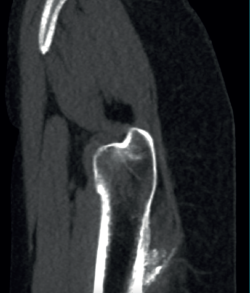

The physical examination revealed a limp-free gait and complete joint balance, with no positive signs of femoroacetabular impingement or inguinal pain. Muscle strength was preserved and similar to that of the contralateral side. She experienced intense pain on palpation of the insertion of the gluteus maximus, referred proximally to the ipsilateral buttock. The pain was reproduced on extension against resistance, and prevented sitting for long periods. Plain radiographic and computed tomography (CT) images revealed calcific tendinosis affecting the aponeurotic prolongation of the gluteus maximus in proximity to its insertion in the upper region of the linea aspera of the femur (Figures 1 and 2) Magnetic resonance imaging (MRI) of the hip showed a labral tear, that proved asymptomatic in the physical examination. In view of the clinical picture of radicular pain, an MRI scan of the lumbar spine and subgluteal space was also performed, ruling out radicular involvement or sciatic neuritis. Her previous treatment over the three years of evolution of the disorder included oral nonsteroidal anti-inflammatory drugs, a specific physiotherapy programme and several ultrasound-guided corticosteroid injections with positive results - though a last session showed no response. Due to the severity and chronicity of the symptoms and their resistance to conservative treatment, surgery was decided to clean and remove the intratendon calcification endoscopically.

Figure 2. Right hip. Sagittal CT view showing calcification of the gluteus maximus at the insertion site on the femur.